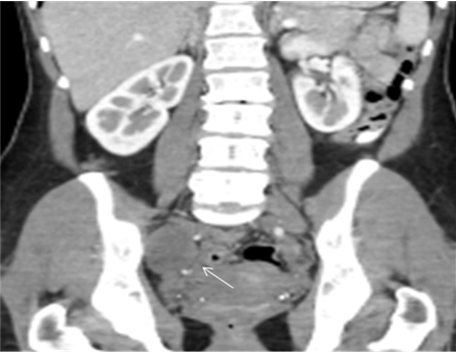

Computed tomography (CT) scan of the pelvis reported the presence of a 4.5 cm nodular lesion, located deep in the right pelvic region (Figure 1). Magnetic resonance imaging (MRI) scan showed a dependent right sciatic nerve lesion (Figure 2). The lesion contacted with the anterior surface of the sacrum and medially displaced the right hypogastric artery (Figure 3).

Figure 1: Contrast enhanced computed tomography scan coronal image. A well-defined hypodense mass within the right hemi-pelvis is noted (arrow).